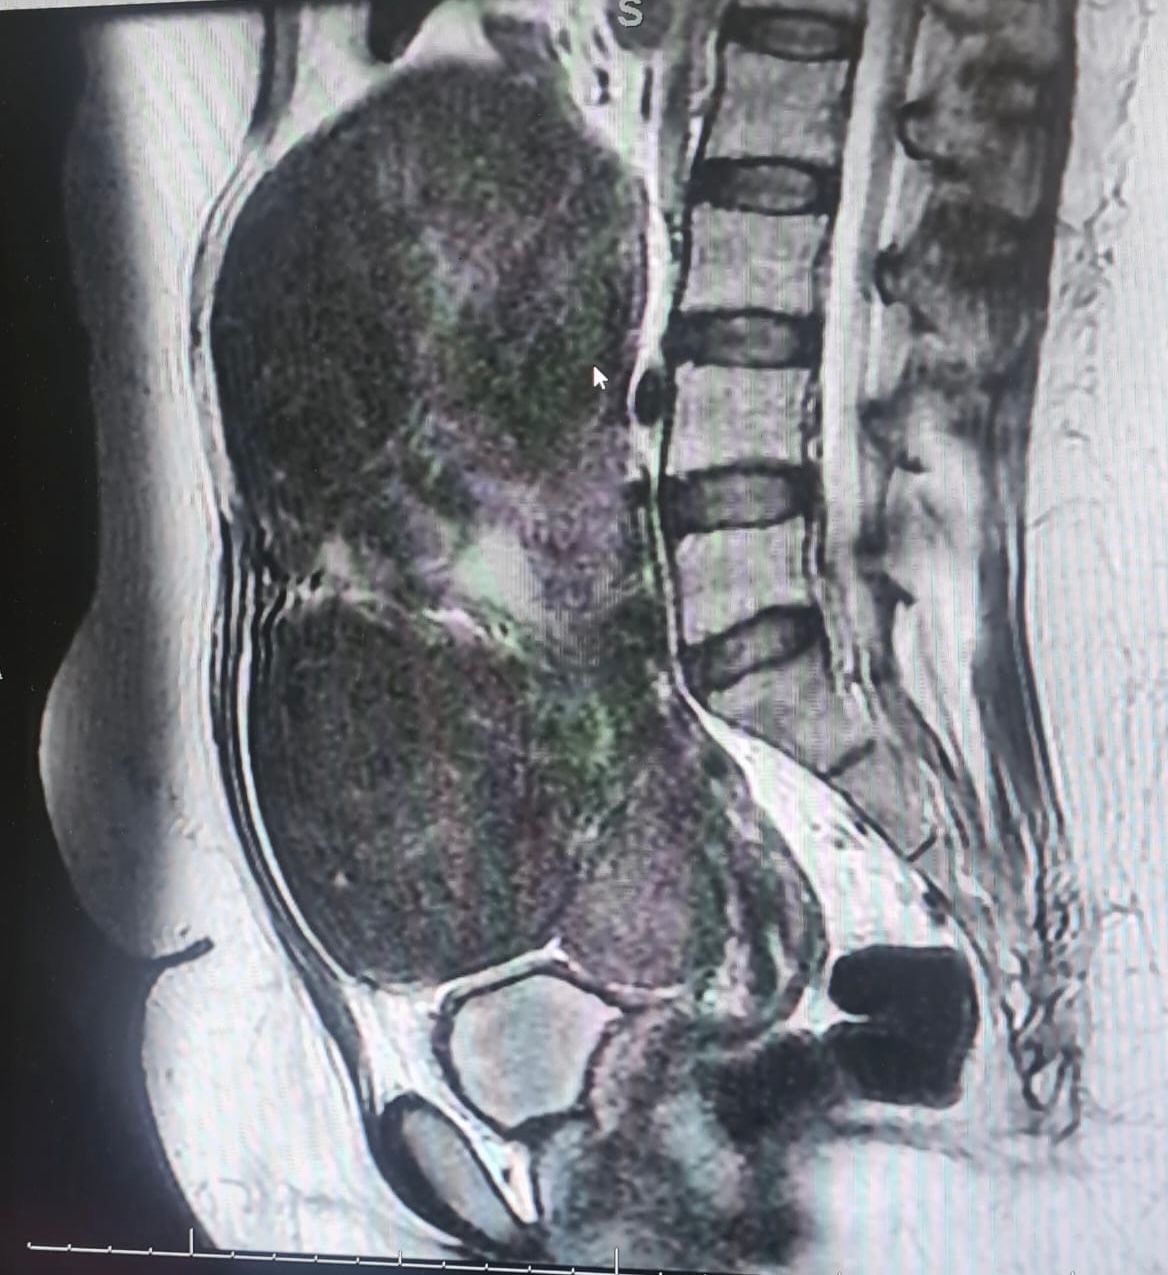

وكانت السيدة تعاني من آلام شديدة وانتفاخ في البطن، مصحوبة بنزيف مستمر استدعى نقل الدم إليها عدة مرات. وبعد إجراء الفحوصات اللازمة، كشفت الأشعة الصوتية والرنين المغناطيسي عن وجود عدة أورام ليفية حميدة تملأ تجويف البطن، أكبرها يتجاوز حجمه 20 سنتيمترًا.